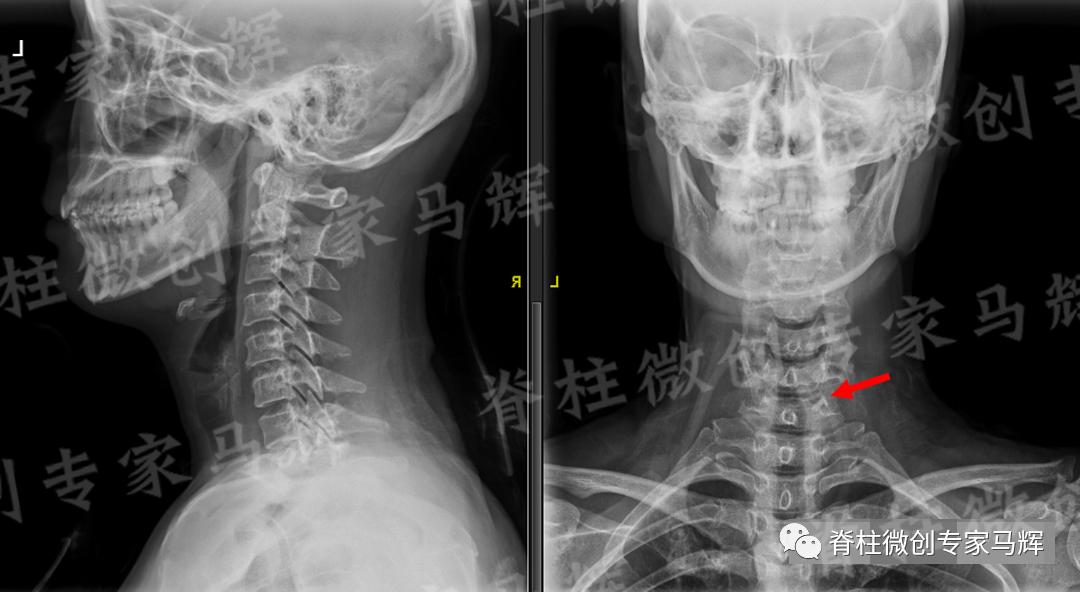

马主任仔细给患者做了检查,发现疼痛范围累及颈背部,及右上臂、前臂至手掌桡侧三指,无胸背部束带感,无行走不稳。根据影像学结果,诊断缪女士患6/7椎间盘突出症,属于神经根型颈椎病。

(术前)